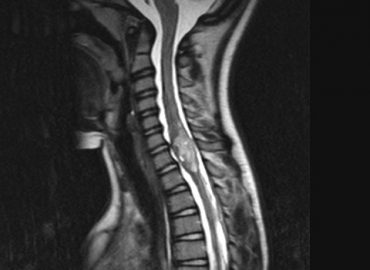

Inestabilidad en la marcha